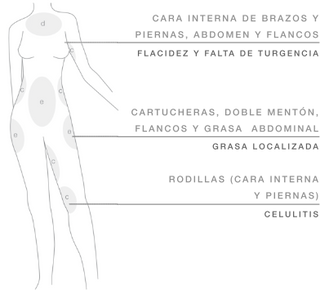

Indications:

* Application zones and relation to microneedle depth:

a. 0,25mm b.< 0,50 mm c.< 1 mm d.< 1,5 mm e.> 1,5 mm